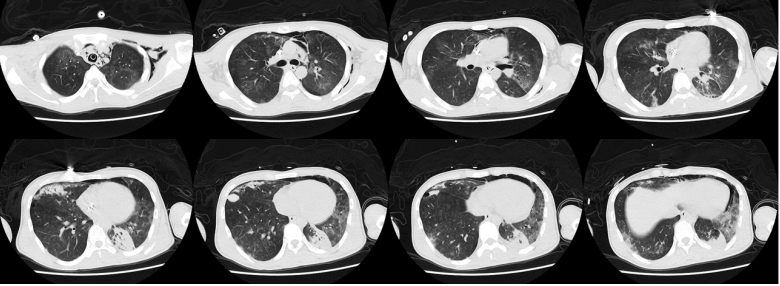

第3周第16天复查胸部CT:患者病变在逐渐吸收,病情较前好转(图5)。撤离ECMO,患者进入康复阶段。期间患者在气管镜下出现气道内右上叶出血。为了避免出血加重,整体调整了抗感染及抗凝治疗,并予西多福韦治疗。复查BALF腺病毒核酸仍为阳性,但患者整体状况、呼吸功能及肺部病变情况在逐渐改善

图片

图5  患者入院后胸部CT(第16天

第23天复查胸部CT:肺内仍有少量气压伤表现以及小结节(图6)第28天复查NGS发现,BALF中腺病毒序列数为22,血中腺病毒序列数为6。再予一次西多福韦。肾功能遗留少量损伤,仍在间断进行肾脏替代治疗治疗。第30天胸部CT可见病变较前明显吸收好转(图7)

图6  患者入院后胸部CT(第23天)

图7  患者入院后胸部CT(第30天)